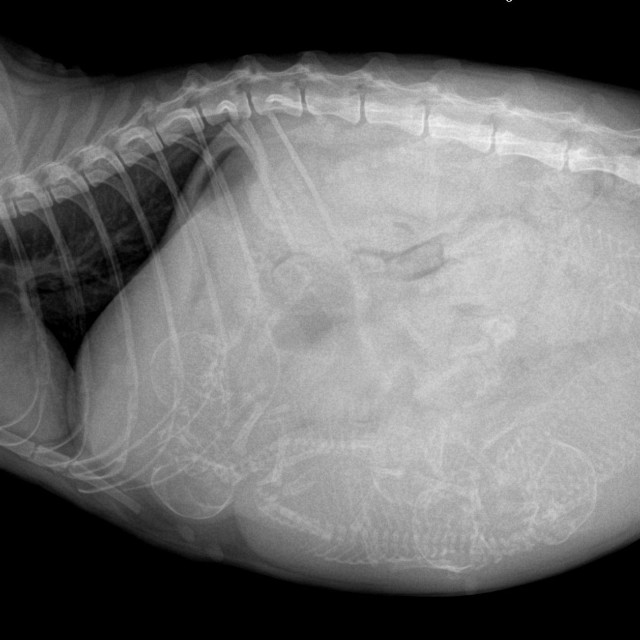

・心疾患による胸水

腹水や胸水があれば、腫瘍・心疾患・肝疾患・感染症・術後合併症などを除外する必要がある。血液検査、画像診断、体液の性状評価など複数の情報を総合的に判断する。

「超音波検査は何百万円もする機器です。腹水の有無だけを見る“確認装置”にしてはいけない。腹腔内臓器を丁寧に評価することが大前提です」